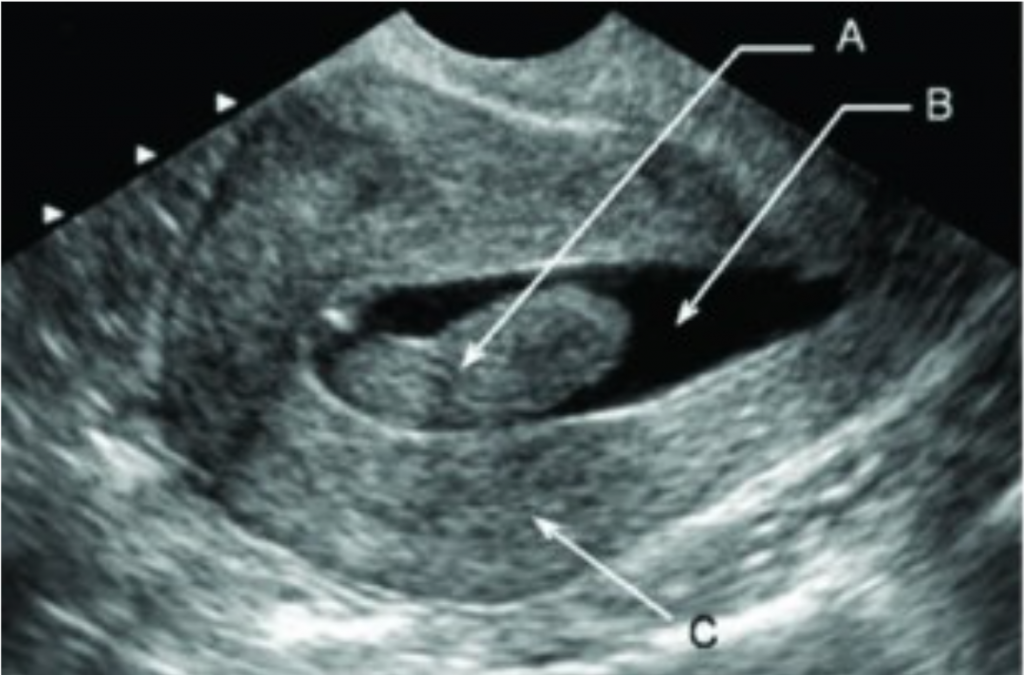

O diagnóstico inicial geralmente é suspeitado por exames de imagem, sendo os mais utilizados:

Entre esses métodos, a histeroscopia é considerada o padrão-ouro, pois permite visualizar diretamente a lesão e, se necessário, já realizar sua remoção no mesmo ato.